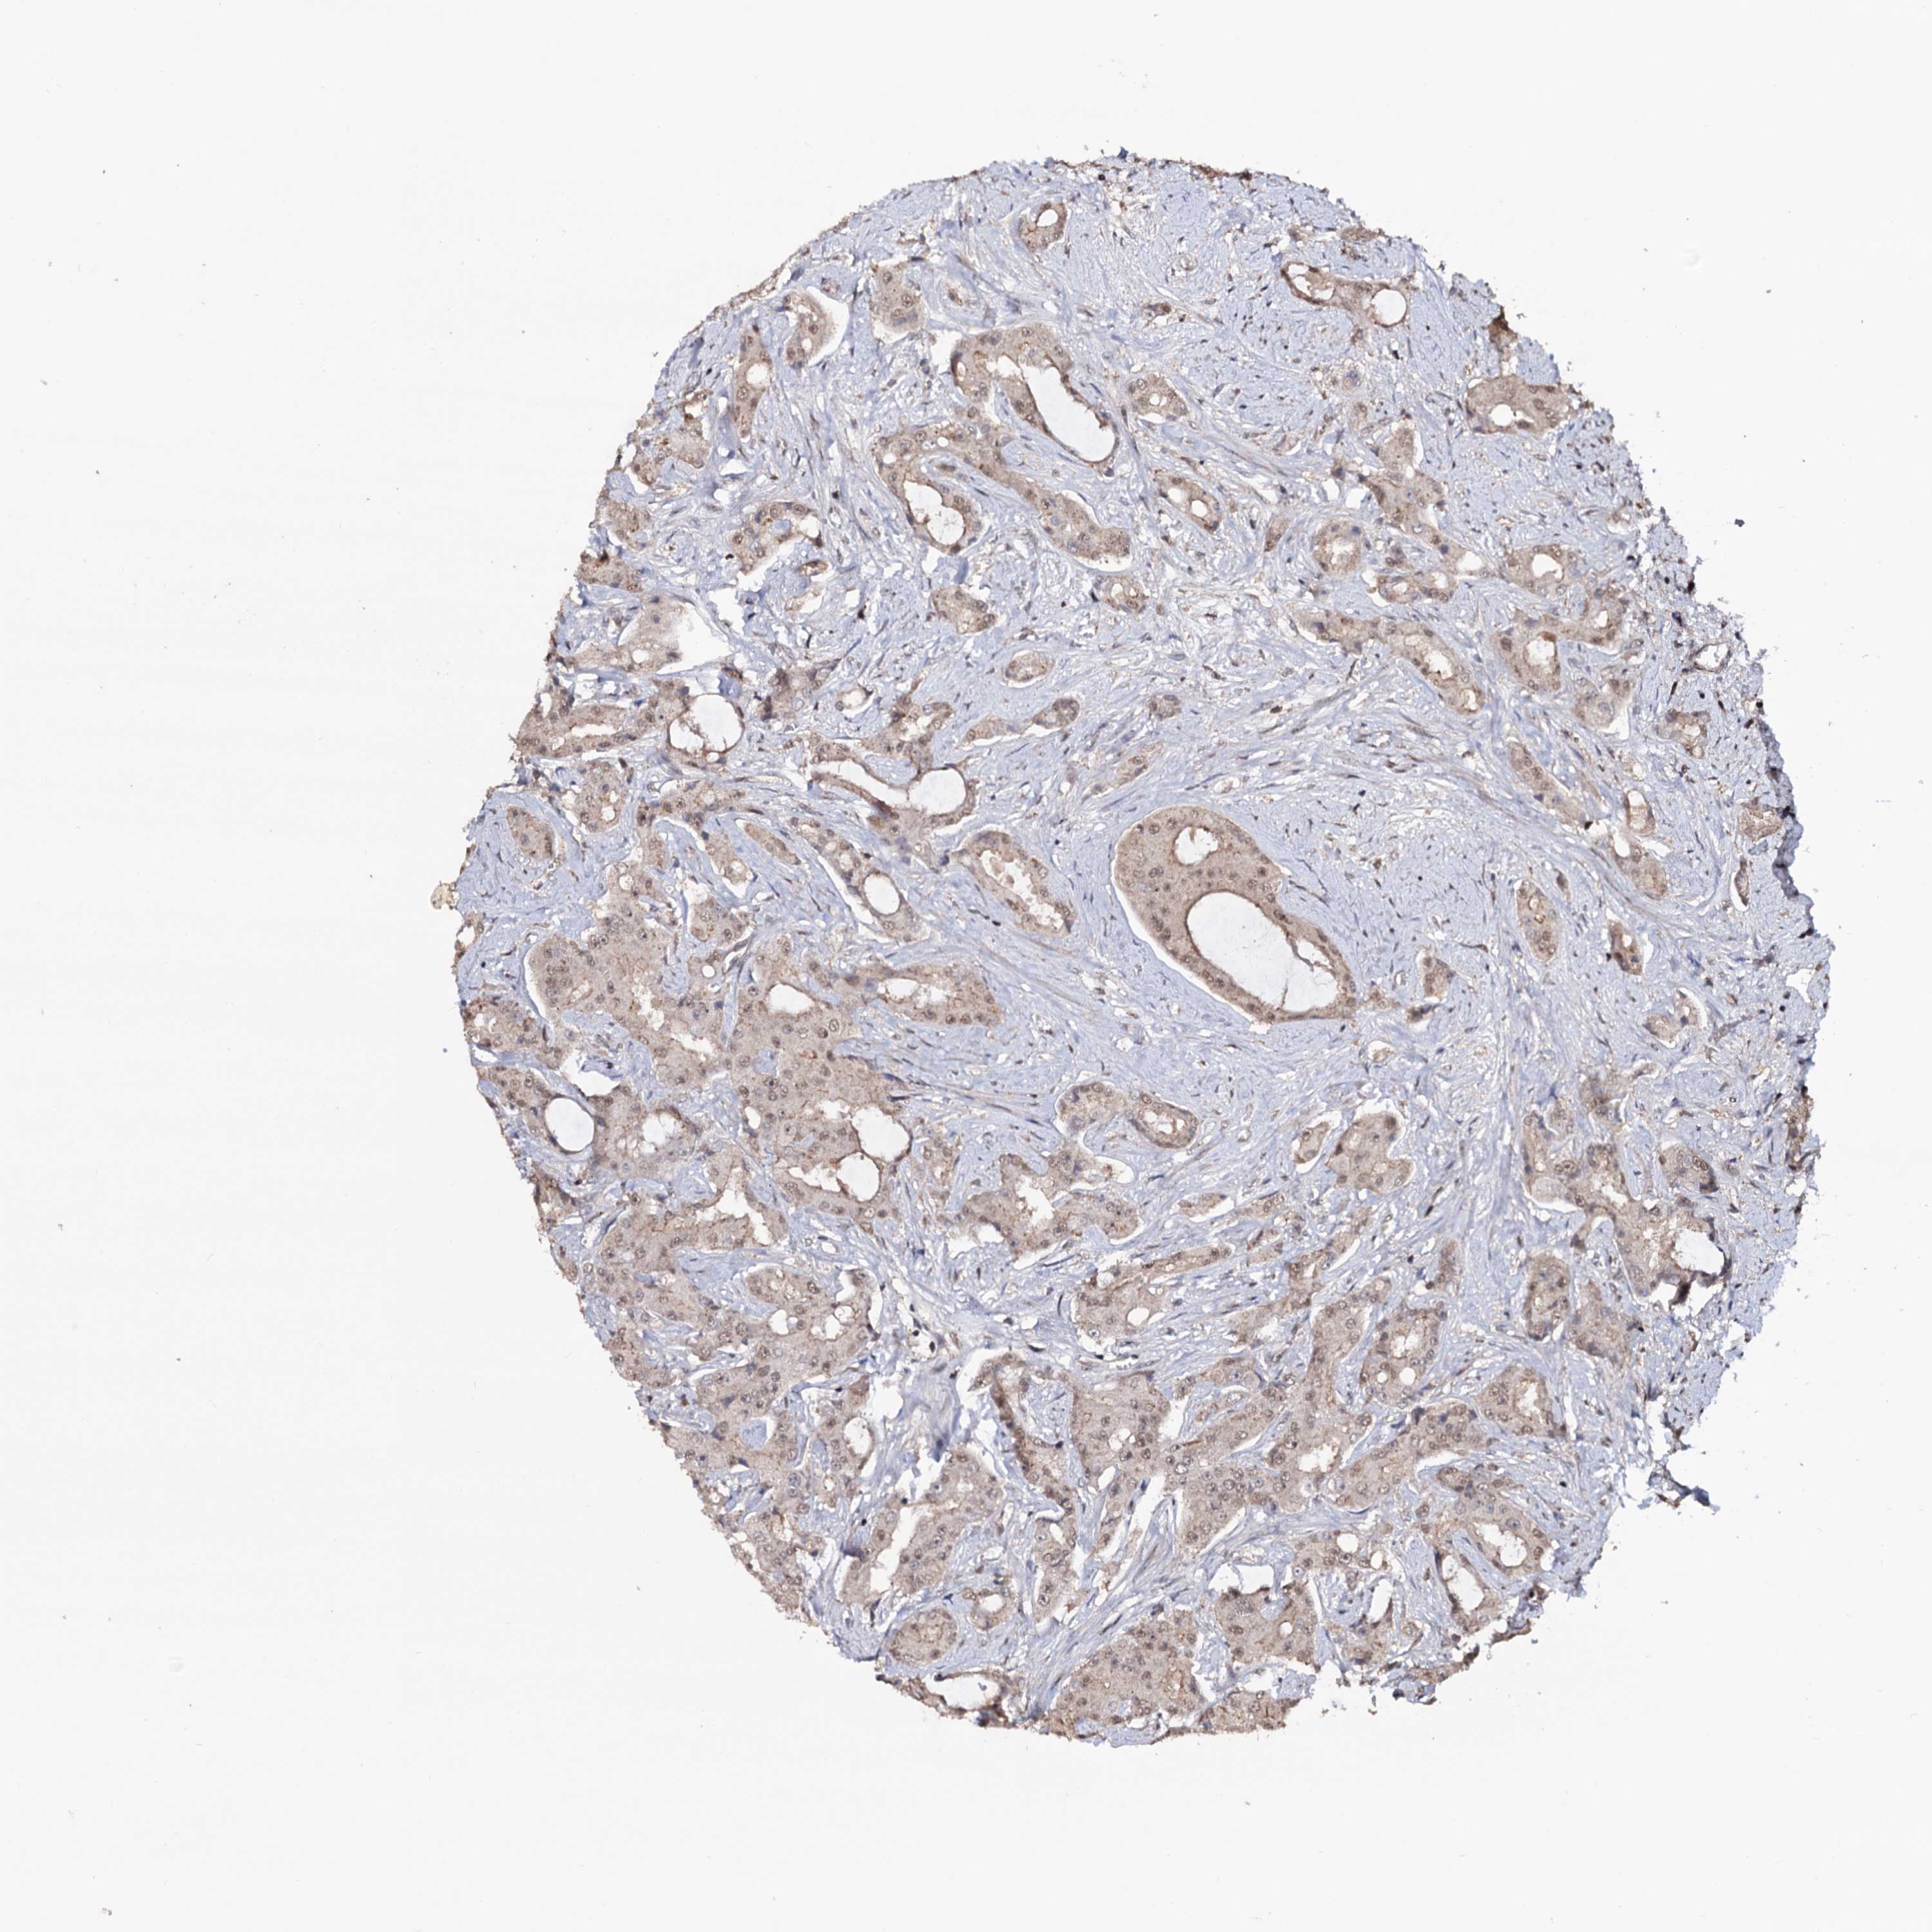

PROSTATE CANCER - Protein expressioni

A mouse-over function shows sample information and annotation data. Click on an image to view it in a full screen mode. Samples can be filtered based on level of antibody staining by selecting one or several of the following categories: high, medium, low and not detected. The assay and annotation is described here.

Antibody stainingi

Antibody staining in the annotated cell types in the current human tissue is reported as not detected, low, medium, or high, based on conventional immunohistochemistry profiling in selected tissues. This score is based on the combination of the staining intensity and fraction of stained cells.

Each image is clickable and will lead to virtual microscopy that enables deeper exploration of all samples and also displays staining intensity scores, fraction scores and subcellular localization as well as patient and tissue information for each sample.

Antibody HPA040398

Staining

High

Medium

Low

Not detected

Intensity

Strong

Moderate

Weak

Negative

Quantity

>75%

75%-25%

<25%

None

Location

Nuclear

Cytoplasmic/membranous

Cytoplasmic/membranous,nuclear

Adenocarcinoma, NOS

Adenocarcinoma, High grade

Adenocarcinoma, Low grade